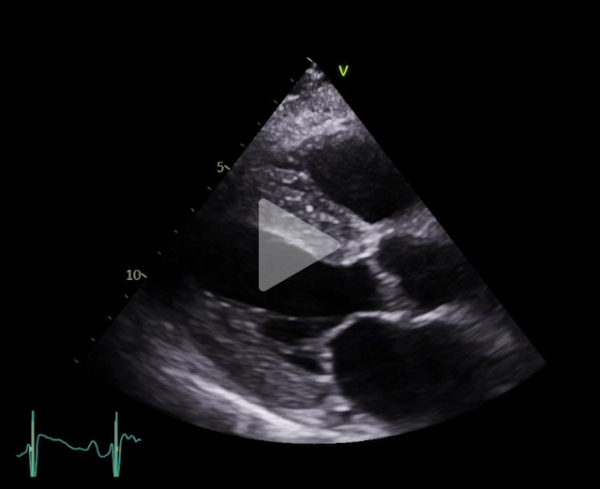

Vidéo 1

FEVG 40% en Simpson biplan, 45-50% visuellement. GLS -7%. Hypokinésie des bases et hyperkinésie de l'apex. VG non dilaté (DTDVG = 35mm, VTDVG =54ml/m2), hypertrophié (SIV = 18.5mm, PPVG = 19mm).

- DC = 3l/min, IC = 1.6l/min/m2 avec CCVG = 21mm et ITV sous Ao = 8cm

- OG dilatée à 40mL/m² (21cm2). OD dilatée à 19cm2

- Valve aortique tricommissurale, fine, pas de sténose ou fuite. Valve mitrale épaissie, pas sténose ou fuite

- Profil mitral restrictif, pressions de remplissage VG élevées (E/A =2.6, E/e’ moy = 22)

- Cavités droites non dilatées (Anneau tric =35mm)

- Fonction VD altérée (TAPSE = 7.7mm, S tric = 5.9cm/s)

- PAPS estimée sur IT modérée à 30 + 15mmHg (TAP 82ms)

- VCI dilatée ( 22mm), non compliante

- Lame péricardique minime